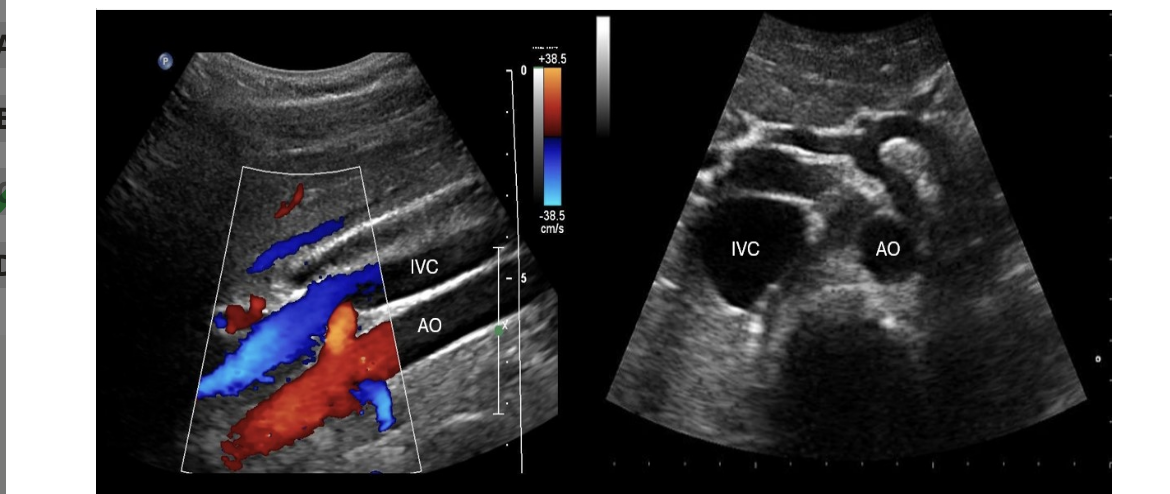

which imaging plane shows the IVC + AO on the same image in a normal pt

.

a) coronal

b) transverse

c) midsagittal

d) coronal + transverse

d. coronal + transverse

![<p>find the left renal artery</p><p>.</p><p>[IVC is on the RIGHT side of AO]</p>](https://knowt-user-attachments.s3.amazonaws.com/a0616f87-f54d-442a-b437-2245e19cdc6b.png)

find the left renal artery

[IVC is on the RIGHT side of AO]

IVC is on the RIGHT side of AO